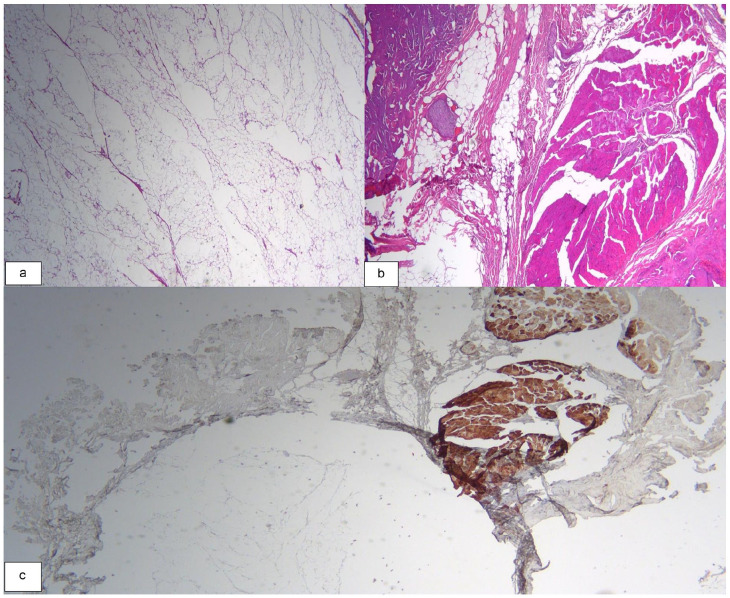

肌内脂肪瘤通常发生在皮下组织,很少影响深层肌肉平面,尤其是头颈部。以下是 3 例涉及胸锁乳突肌的肌肉内脂肪瘤病例。前两名患者表现为无痛、可触及的肿块,经影像诊断证实为环绕性肌内脂肪瘤。其中一名患者接受了手术治疗,另一名患者接受了保守治疗,并进行了监测和密切随访。第三位患者报告吞咽困难,并伴有偶尔的呼吸困难和轻微疼痛。肿块被确定为浸润性脂肪瘤,并进行了手术切除。第一例和最后一例患者的肿瘤完全切除,6 个月后无复发。对第二个病例进行了 3 个月和 6 个月的连续随访,结果没有发生间隔变化。我们报告了胸锁乳突肌肌内脂肪瘤的最大病例系列,以加深我们对这一罕见病例的了解。

Intramuscular lipomas, typically found in subcutaneous tissue, rarely affect deeper muscular planes, especially those of the head and neck region. The following are 3 cases of intramuscular lipomas involving the sternocleidomastoid muscle. The first 2 patients presented with painless, palpable masses confirmed by diagnostic imaging as well-circumscribed intramuscular lipomas. One was treated surgically, while the other was managed conservatively with monitoring and close follow-up. The third patient reported dysphagia associated with occasional dyspnea and mild pain. The mass was identified as infiltrative lipoma and was resected surgically. Complete tumor removal with no recurrence at 6 months was observed for the first and last cases. The second case was serially followed at 3 and 6 months with no interval changes. We report the largest case series on intramuscular lipomas of the sternocleidomastoid muscle to enhance our understanding of this rare entity.